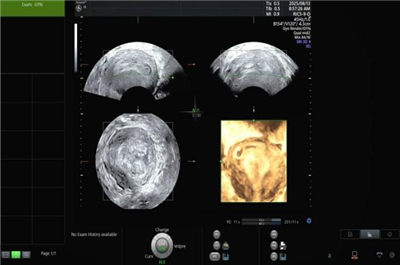

规范现有业务诊断标准,同步指导开展肌骨超声、超声造影、宫腔三维超声及盆底超声。